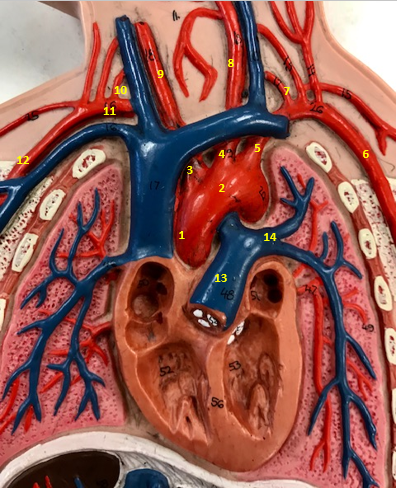

Aorta

Name #2

Brings blood out of left ventricle

Function of aorta

Brachiocephalic artery

Name #3

Supplies oxygenated blood to right arm shoulder neck and head

Function of brachiocephalic artery

Left common carotid artery

Name #4

Supplies oxygenated blood to left neck and head

Function of left common carotid artery

Left subclavian artery

Name #5

Supplies oxygenated blood to left arm shoulder

Function of left subclavian artery

Left axillery artery

Name #6

supplies blood to left armpit and upper limb

Function left axillary artery (6)

Left vertebral artery

Name #7

Supplies blood to brain and spinal cord

Function of left vertebral artery (7)

Left common carotid artery

Name #8

Supplies blood to left neck and head

Function of left common carotid artery (8)

Right common carotid artery

Name #9

Supplies oxygenated blood to right neck and head

Function of right common carotid artery (9)

Right vertebral artery

Name #10

Supplies blood to brain and spinal cord

Function of right vertebral artery (10)

Right subclavian artery

Name #11

Supplies blood to right arm and shoulder

Function of right subclavian artery

Right axillery artery

Name #12

Supplies blood to right armpit and upper limb

Function of right axillery artery (12)

Pulmonary trunk

Name #13

Bring blood out of right ventricle to lungs

Function of pulmonary trunk (13)

Left pulmonary artery

Name #14

Bring blood to left lung

Function of left pulmonary artery (14)